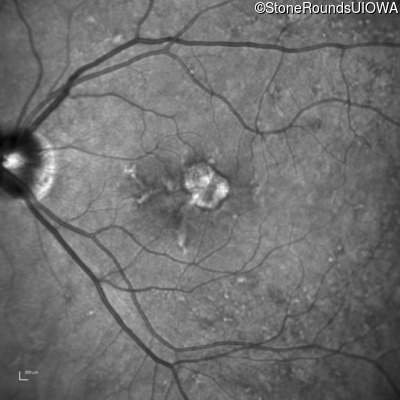

Blue Autofluorescence - Right - 20/25

Exemplar

Blue Autofluorescence - Left - 20/40 -1